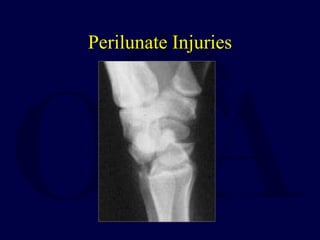

Perilunate Injuries

Mechanism of Injury

โ€ข Load applied to hand forcing the wrist into extension and

ulnar deviation

โ€ข Severe ligament injury necessary to tear the distal row

from the lunate to produce perilunate dislocation

โ€ข Injury progresses through several stages:

โ€“ usually begins radially & destabilizes thru body of scaphoid (w/

fx) or thru scapholunate interval (w/ dissociation)

โ€“ force is transmitted ulnarly thru the space of Poirier (between

lunate and capitate volarly)

โ€“ next force transmission disrupts the luno-triquetral articulation